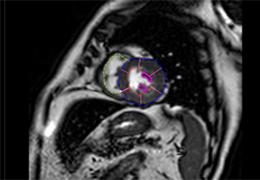

High-quality and fast 3D reconstruction and 3D rendering

Performs 3D reconstruction and volume rendering.

Multi-planar slicing.